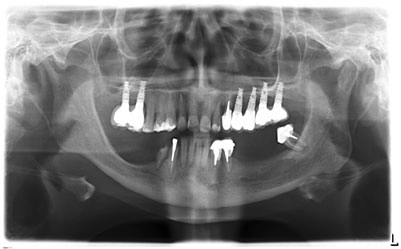

Пациентка C. 48 лет.

Жалобы. При первичном обращении в стоматологическое отделение клиники АО «Медицина» в июне 2018 г. – жалобы на отсутствие зубов.

17, 16, 24, 25, 26, 27 – дентальные имплантаты, покрытые коронками;

37, 36, 35, 45, 46, 47 – отсутствуют;

металлокерамические мостовидные протезы с опорой на 34-33, 43-44 (патологическая подвижность III степени, герметизм нарушен);

23 – под металлокерамической коронкой;

на нижней челюсти – бюгельный протез.

С помощью Пьезотома проведена операция латерализации и постеориоризации нижнечелюстного нерва в области 35-37 и 45-47.

С помощью боров и костных конденсоров XiVE сформированы 7 лож имплантатов. Введены имплантаты XiVE в области 35, 36, 37 – D3,4/L13; 45, 46, 47 – D3,4/L9,5; 44 – D3,8/L9,5; 43 – D3,8/L11.